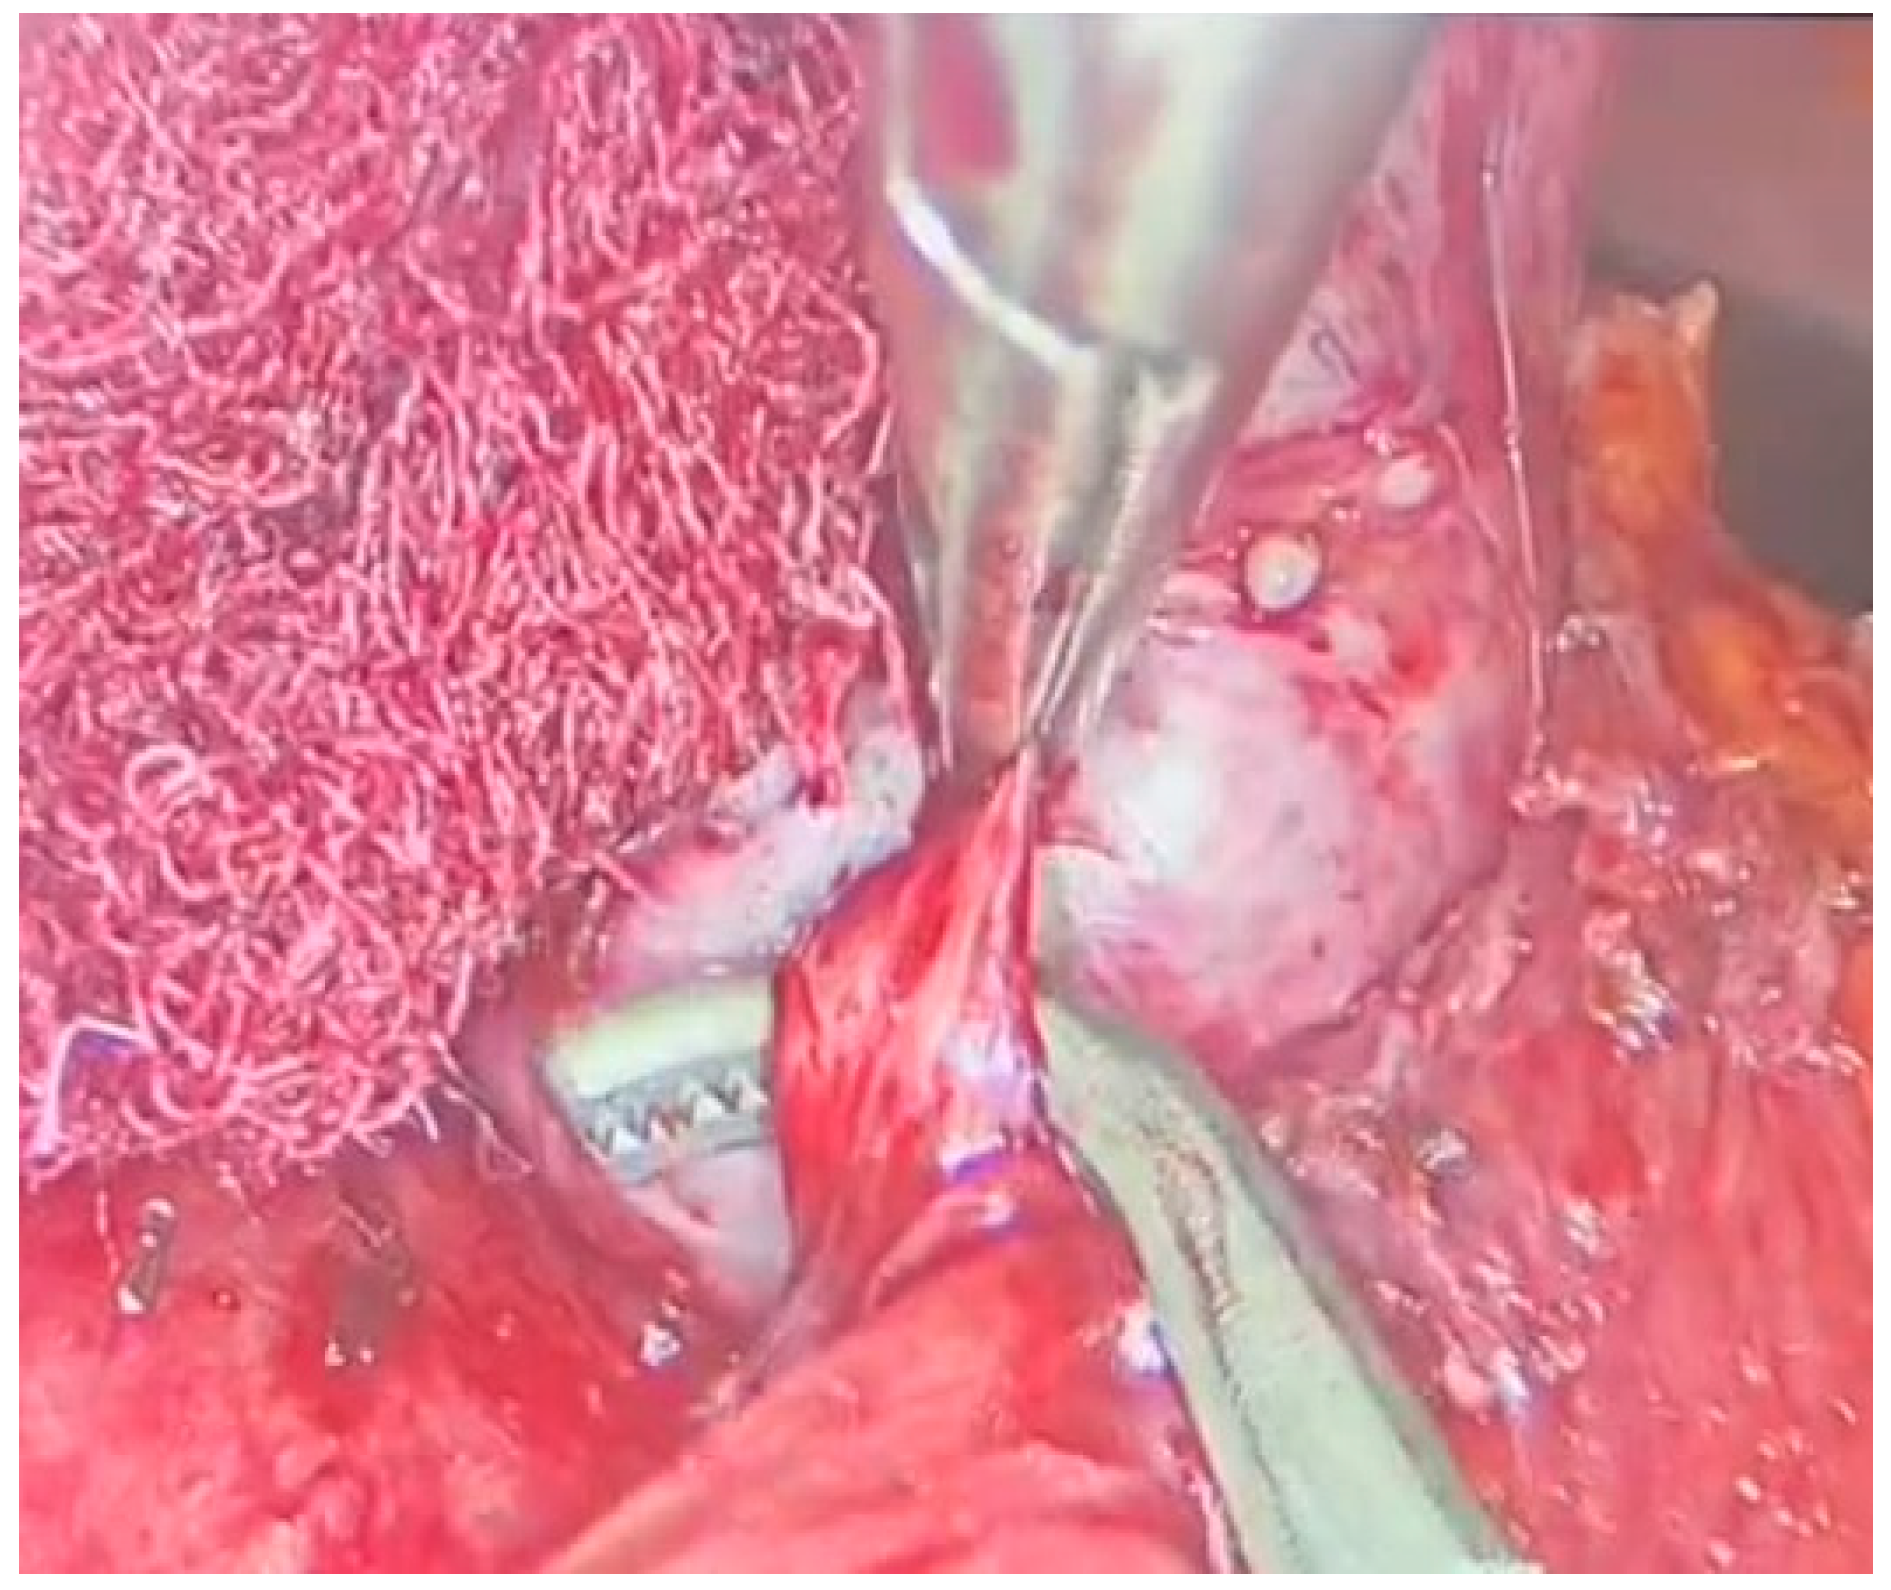

With meticulous dissection and the use of a radiofrequency instrument, the mass was successfully freed from adhesions [Figure 3]. Afferent vessels were ligated and sectioned, and the mass was completely excised using an endobag.

Figure 3.

Laparoscopic adrenalectomy, dissection from the residual adhesions.